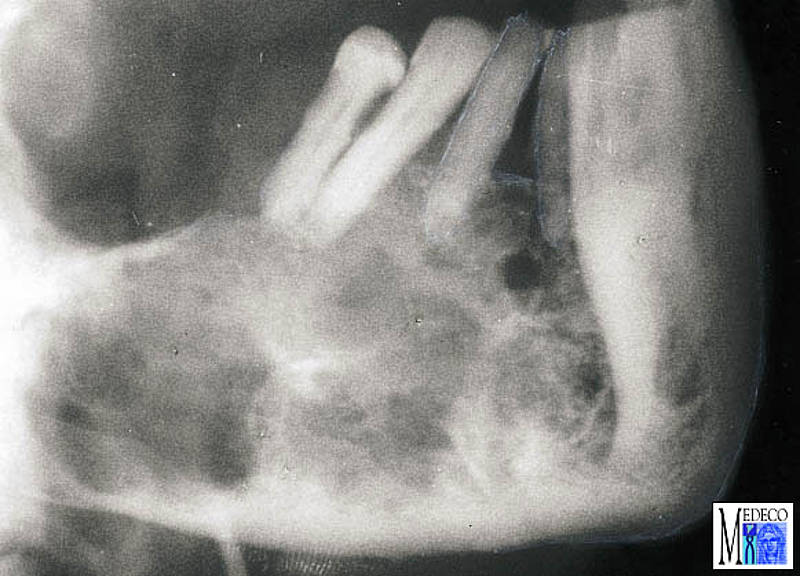

Mesenchymale benigne Tumoren From www.medeco.de

Odontogene Tumoren

Mesenchymale benigne Tumoren